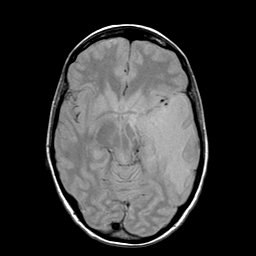

Metastatic bronchogenic carcinoma: proton density-weighted MR -- Slice #9

[Home][Help][Clinical] Slice 9